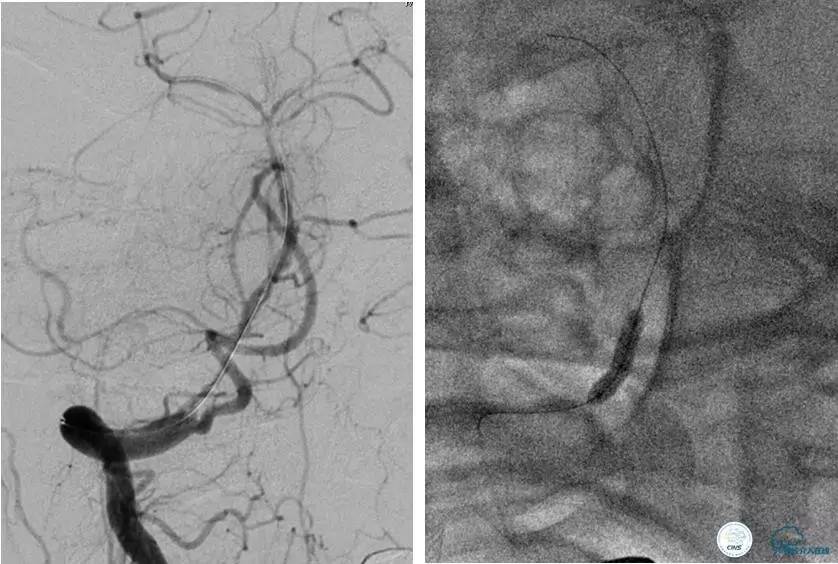

病例5

患者:49岁男性,左侧偏瘫1个月,药物治疗、康复训练效果不好,转我院,肌力0~1级。

core-clilnical明显不匹配,是介入开通的合适患者。

造影评价血管、判断闭塞段,微导丝小心穿过闭塞段,微导管造影,交换技术,球囊扩张,Enterprise支架。在后扩张时导丝刺破M3段血管,蛛网膜下腔出血(SAH)。

微导管进入破裂血管,栓塞弹簧圈1枚,出血停止,结束手术。继续双抗,术后2天肌力2级,神经功能恢复明显加快。

术后即刻和6天后CT,患者无明显临床症状。

半年后复查造影,无支架内再狭窄,可见弹簧圈,患者恢复至自己柱杖行走。